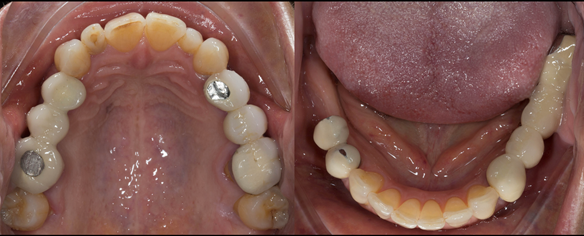

This newsletter describes in step by step detail Angela's transition through immediate partial dentures to crown supported definitive metal based dentures.

This 58 year old woman was referred to me by her general dental practitoner for treatment.

- Generalised Periodontitis; Stage 4, Grade C, Currently Unstable. Risk Factors: Type 1 diabetes. 16, 17 - hopeless prognosis. 14, 24, 26, 27, 34, 37, 44 - guarded prognosis

- Poor marginal fit and poor appearance of crowns and bridgework

The clinical situation and treatment process is shown in detail below with photographs. I (Finlay Sutton) provided the clinical work and Rowan Garstang provided the technical work.